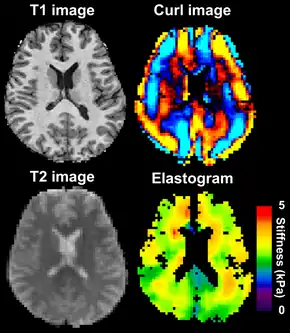

Magnetic resonance elastography of the brain. A T1 weighted anatomical image is shown in the top-left, and the corresponding T2 weighted image from the MRE data is shown in the bottom-left. The wave image used to make the elastogram is shown in the top-right, and the resulting elastogram is in the bottom-right.

MRE is conducted in three steps: first, a mechanical vibrator is used on the surface of the patient's body to generate shear waves that travel into the patient's deeper tissues; second, an MRI acquisition sequence measures the propagation and velocity of the waves; and finally this information is processed by an inversion algorithm to quantitatively infer and map tissue stiffness in 3-D.[2][3] This stiffness map is called an elastogram, and is the final output of MRE, along with conventional 3-D MRI images as shown on the right.[2]

MRE of the brain [27] was first presented in the early 2000s.[28][29] Elastogram measures have been correlated with memory tasks,[30] fitness measures,[31] and progression of various neurodegenerative conditions.[27] For example, regional and global decreases in brain viscoelasticity have been observed in Alzheimer's disease[32][33] and multiple sclerosis.[34][35] It has been found that as the brain ages, it loses its viscoelastic integrity due to degeneration of neurons and oligodendrocytes.[36][37] A recent study looked into both the isotropic and anisotropic stiffness in brain and found a correlation between the two and with age, particularly in gray matter.[38]